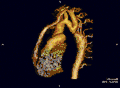

- Mit der Spiral-Computertomografie ist gleichfalls eine 3-D-Rekonstruktion möglich.

Die beiden zuletzt genannten Untersuchungsmethoden dienen der anatomischen Rekonstruktion bei zusätzlich vorliegenden Aortenbogenfehlbildungen bzw. Variationen.

Koarktation der Aorta mit verschiedenen bildgebenden Verfahren:

B – Kontrastverstärktes 3D-CT-Angiogramm mit einem leicht verengten Bare-Metal-Stent (Pfeil), der teilweise den Ursprung der linken Arteria subclavia bedeckt. Die Pfeilspitze zeigt ein subtiles Pseudoaneurysma am distalenEnde des Stents.

C – Kontrastverstärktes 3D-Angiogramm mit Aortenbogenhypoplasie und Koarktation mit posteriorem Bypass-Transplantat (Pfeil)